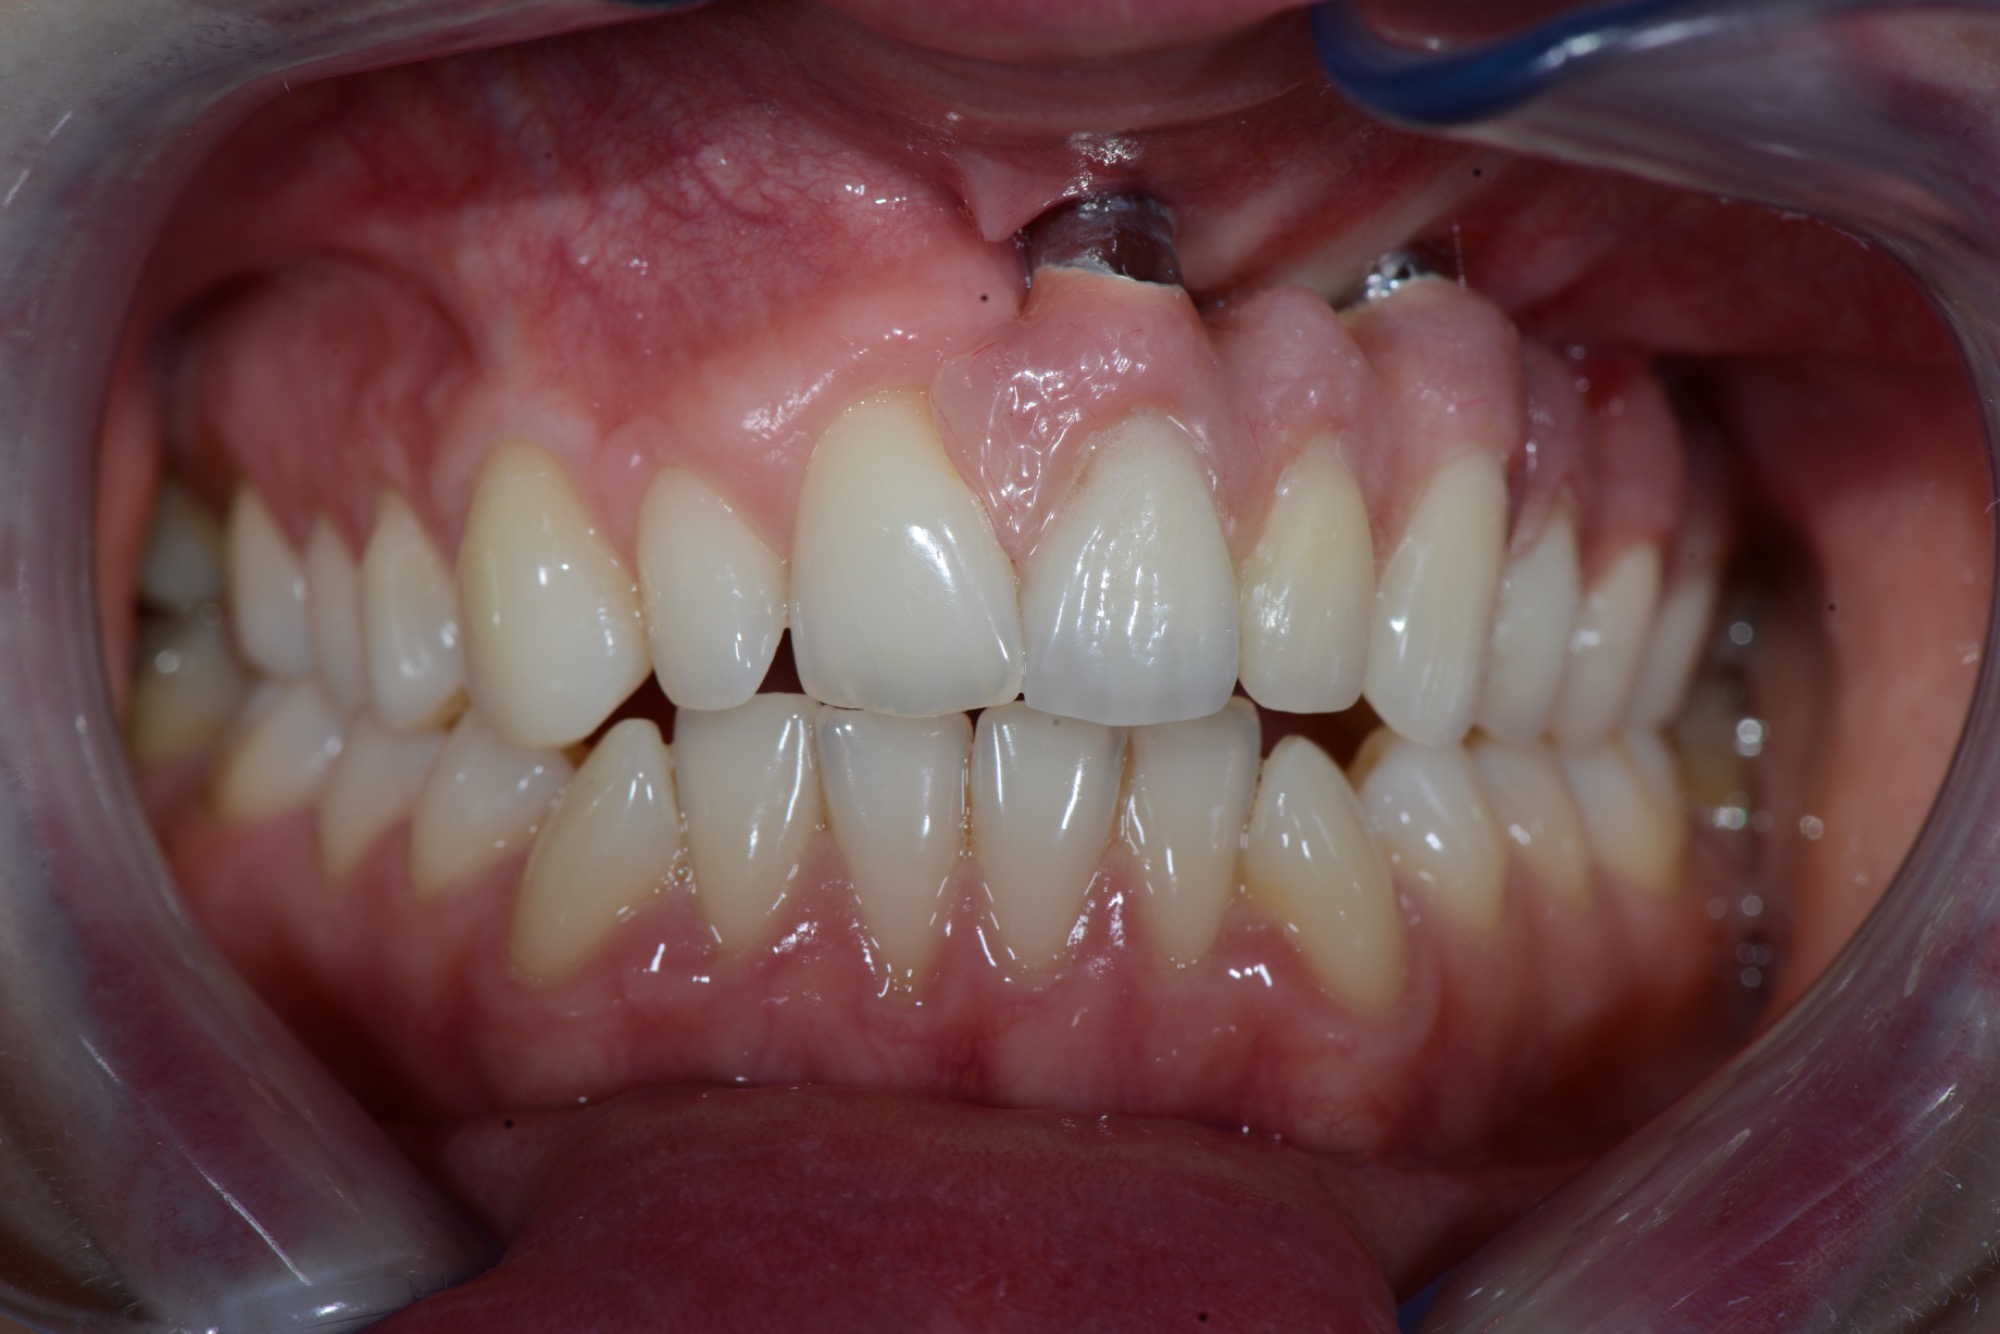

Teleskopierende Oberkieferbrücke mit Vorher- und Nachher-Situation des Patienten.

Kombination aus implantatverankerten Brücken und auf natürlichen Stümpfen verankerten Kronen.

Frontzahnkrone auf Implantat zum Lückenschluss des seitlichen Frontzahnes.